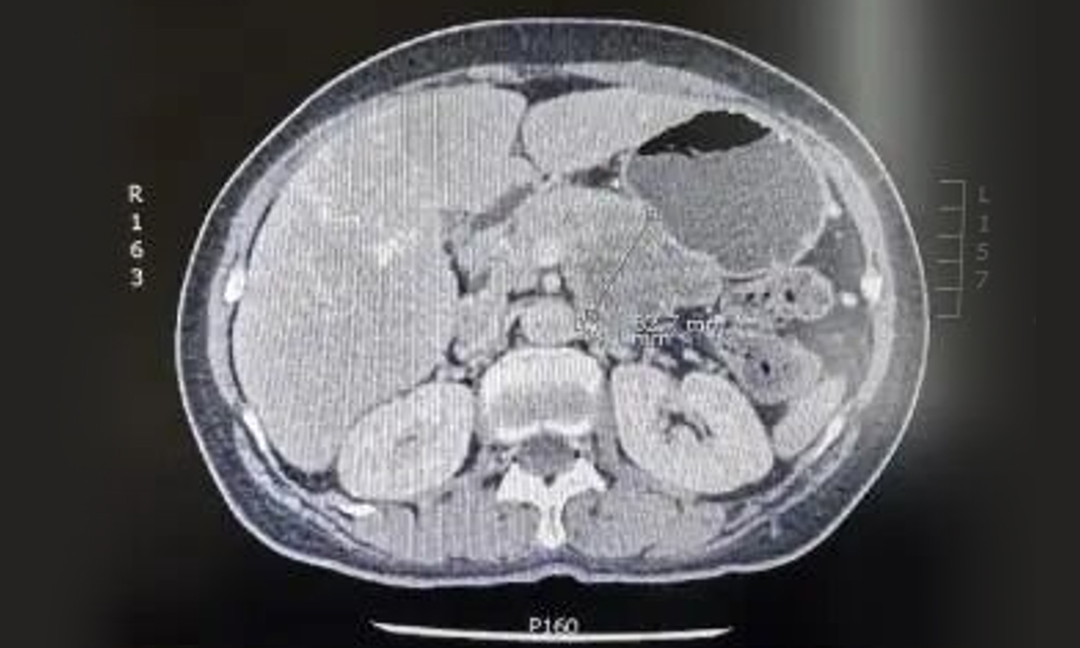

患者女,76岁,因食欲下降骤减和莫名乏力在当地医院进行检查。中上腹增强CT检查发现胰体尾部占位,较大截面范围约6.5cm ×4.6cm,穿刺活检病理提示:胰腺导管腺癌。

▲ CT显示胰体尾部肿瘤

▲ CT显示胰体尾部肿瘤